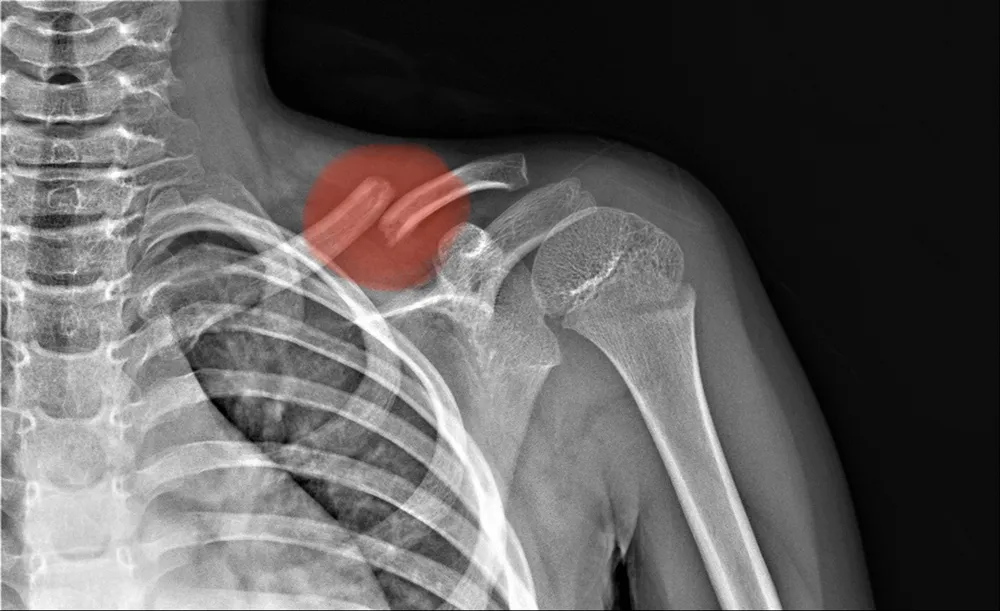

- Chụp X-quang: Chụp X-quang cũng có thể cho biết chính xác vị trí gãy, mức độ nghiêm trọng và liệu có xương nào khác bị gãy hay không.